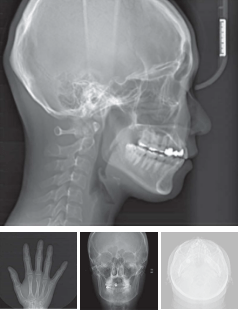

Cephalometric

- 高速スキャン

- 小児患者のモーションアーチファクトを最小限に抑えた4秒高速スキャン。

- 後頭部拡張スキャン

- 様々な矯正分析に対応できる後頭部画像領域を取得できます。

- 高解像度画像

- 軟組織と骨組織の画像表現技術をそれぞれ適用し、トレースポイントを見つけやすい高解像度画像を取得できます。

- 撮影モード

- Lateral, Lateral Wide, SMV, Carpus, PA

- アップグレード

- RAYSCANα(3D Edge)モデルは、セファロをアップグレード出来る仕様で設計されています。